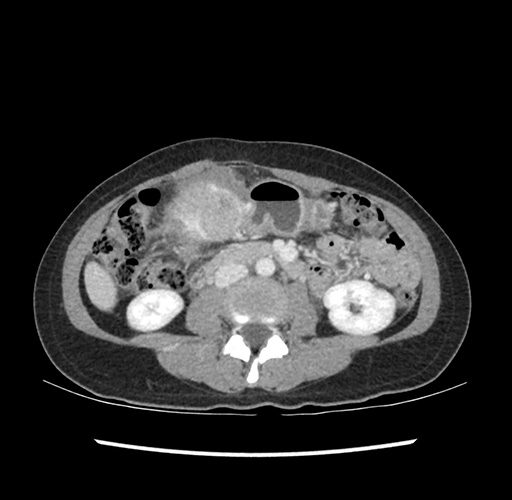

Imaging Analysis

Look through the patient's CT scan to identify any areas of concern for the necessary procedure.

Based on your CT findings, which issue(s) would give reason for "planned slowing down moment(s)" in this case?